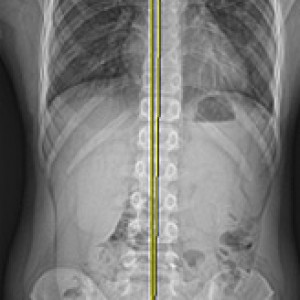

검사부터 다른 당당

“당당은 뼈만 보지 않습니다.”

근육과 근막의 정렬을 함께 진단하며, 풀 스파인 촬영을 통해 머리부터 모든 고관절, 발의 정렬까지 함께 파악하여 개개인에 맞는 전신 치료법을 설계합니다.

전신 엑스레이 검사

다리길이 엑스레이 검사